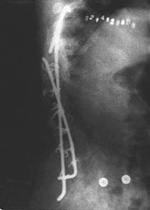

Another operation in 1987 left Si with two scars. The one on her side was some 40 centimeters long; the other circled her waist from her abdomen to her back. After placing wires to hold a steel rod against her spine, doctors removed a piece of bone from her ribs and used it to graft the rod in place. The operation lasted more than eight hours.

Si was confined to bed for an entire year after the surgery, only to have the spinal curvature recur. The hook on the top of the rod protruded, making it painful either to sit or lie down. In 1991, Si went back into the operating room to have two more steel rods inserted along her spinal column.